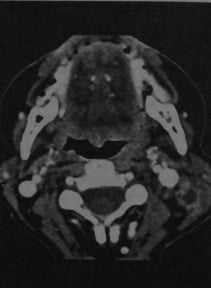

Лимфаденит шейный. КТ в горизонтальной проекции: увеличенные лимфатические узлы с образованием центральных полостей. Края лимфатических узлов нечеткие, кзади от левой яремной вены и медиальнее грудино-ключично-сосцевидной У мышцы определяется кольцо усиления.